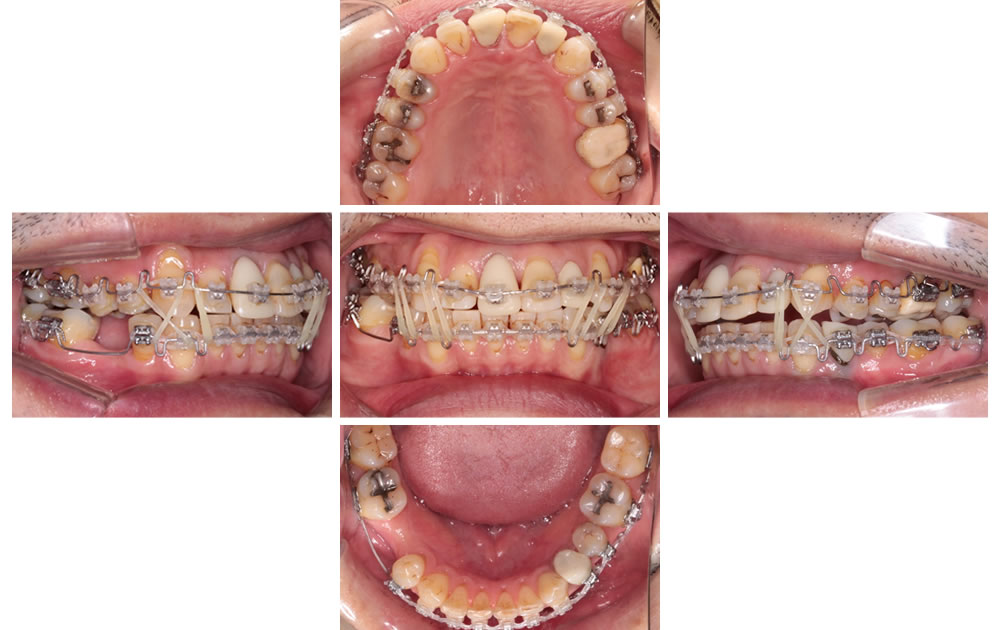

拡大床とワイヤーによる非抜歯矯正の症例(41歳男性 治療期間約2年)

▼こちらの患者さまは、歯並びと咬み合わせを治したいとのことでご来院されました。他院の矯正専門医より、矯正治療に伴う抜歯が必要と診断された症例でしたが、拡大床と3次元ワイヤー矯正で歯を抜くことなく理想の歯並び・咬み合わせへと改善できました。

(※保存不可能な歯は抜歯しています)

初診時の口腔内です。上顎のスペースが少なく、歯が正常に並んでいない。真ん中がズレており、噛み合わせが悪く、よく噛めないという状態でした。